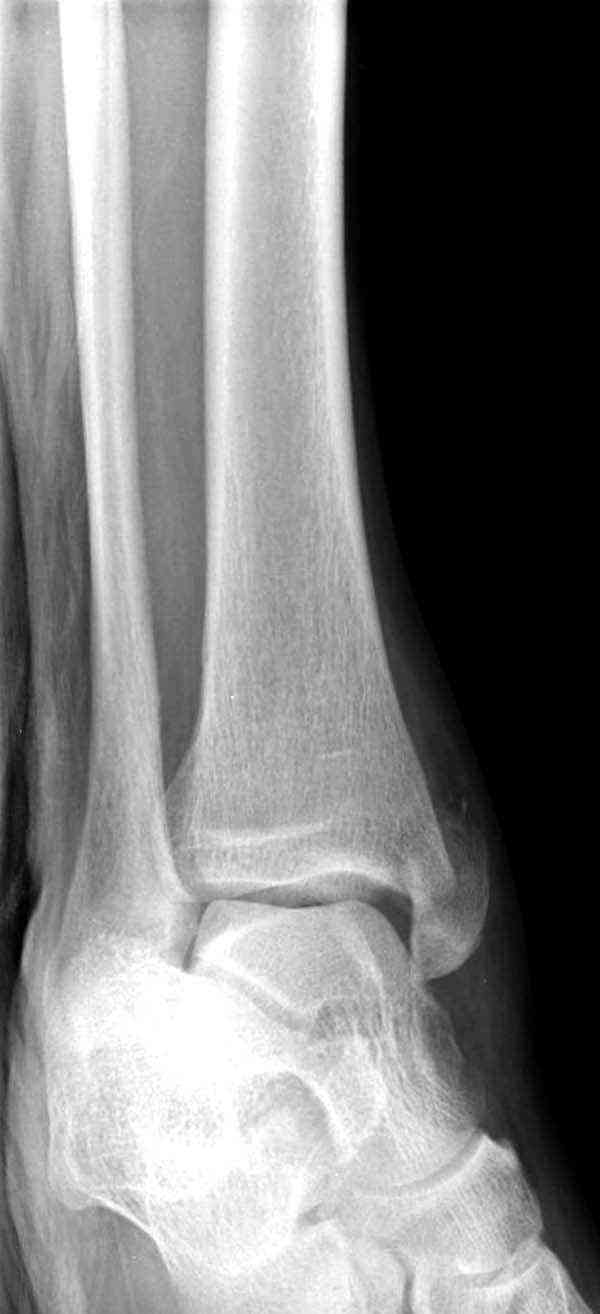

Случай прошлого года:пациентка-молодая ,крупная женщина ,30лет.Травма в начале апреля 2009г-пронационный перелом лодыжек с подвывихом стопы.Ко мне обратилась через 35 дней,прооперирована 22.05.2009г.Внутренняя лодыжка фиксирована по Веберу,наружная реконструктивной пластиной с наложением болта-стяжки.Иммобилизация "сапожок" в течении месяца,затем пригипсовано "стремя".Гипс снят 10.07.2009г

Достаточно быстрое восстановление функции.В октябре 2009г-почувствовала боль,в области рубца над гайкой открылся свищ.На Р-граммах-консолидация переломов и смещение гайки по стяжке.10.11.2009г-конструкции удалены,санация,заживление ран.В настоящее время пациентку ничего не беспокоит.На операции-раскручивание гайки-болталась на конце стяжки.Вопросы:какой механизм раскручивания и что я неправильно сделал?Свои версии:1)в области синдесмоза успела образоваться рубцовая ткань,которая при движении в суставе"пружинила",поскольку голеностопный сустав является спиральным, то и биомеханика подобна кривошипному механизму.2)Реконструктивная пластина не "реконструировалась" по форме лодыжки.Наложил,как есть.То есть подпружинивала сама пластина.Ну,это мои догадки.Что нужно,чтобы избегать впредь таких,пусть и не "страшных"осложнений:Рассверливать через лодыжку область синдесмоза?Ставить шайбу-гровер?Тщательно моделировать пластину?Прилагаю сравнительные снимки-сразу после операции и перед удалением конструкции.

Визуально никаких вопросов по репозиции не было.Да и на основании чего сомнения,что наружная лодыжка не полностью репонирована или прорезалась проволка ???Я не вижу...Снимок после репозиции справа.

Раз ,есть желание посмотреть другую проекцию выкладываю-ну лучшего качества нет...